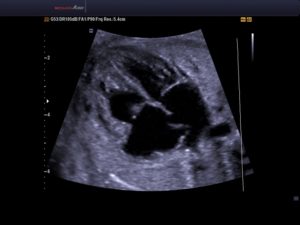

Эхокардиография плода (фетальная эхокардиография) – специальная ультразвуковая методика, позволяющая в процессе беременности исследовать морфологические и функциональные особенности сердца плода. Позволяет еще до рождения, неинвазивно выявлять врожденную патологию сердца. Обычно выполняется на 18-24 неделе гестации.

ЭхоКГ плода дает возможность оценить состояние полостей сердца, межпредсердных перегородок сердечных клапанов, магистральных сосудов. Применяется для пренатальной (дородовой) диагностики врожденных пороков сердца и нарушений сердечного ритма у плода, что дает возможность оптимально спланировать дальнейшую тактику их лечения.

При выполнении ЭхоКГ используются различные режимы сканирования, позволяющие детально визуализировать сердце плода:

- двухмерная эхокардиография – используется для оценки анатомии основных структур сердца (камер, клапанов, главных артерий и вен). Изображение выводится в виде двухмерного среза.

- М-эхокардиография – позволяет наблюдать интракардиальные структуры (стенки камер сердца, створки клапанов) в режиме движения, оценивать систолическую функцию желудочков.

- Допплерэхокардиография – используется для изучения гемодинамики в сосудах и камерах сердца, а также оценки сердечного ритма. Проводится в режиме ЦДК и импульсной допплерографии.

Стандартное эхографическое исследование включает оценку четырехкамерного среза сердца (положения сердца в грудной полости, строения желудочков и предсердий, сформированности межжелудочковой и межпредсердной перегородок, движений створок митрального и трикуспидального клапанов), главных артерий (взаиморасположение и диаметр аорты и легочного ствола), характеристик сердечной деятельности (ЧСС, ритмичности предсердно-желудочковых сокращений). С протоколом эхокардиографии плода в обязательном порядке должен быть ознакомлен акушер-гинеколог, наблюдающий беременность, который прокомментирует женщине результаты диагностики, объяснит все имеющиеся риски.